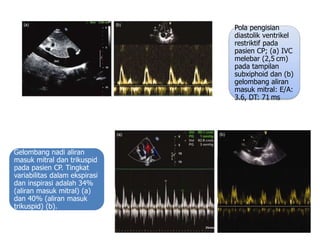

Pola pengisian

diastolik ventrikel

restriktif pada

pasien CP; (a) IVC

melebar (2,5 cm)

pada tampilan

subxiphoid dan (b)

gelombang aliran

masuk mitral: E/A:

3.6, DT: 71 ms

Gelombang nadi aliran

masuk mitral dan trikuspid

pada pasien CP. Tingkat

variabilitas dalam ekspirasi

dan inspirasi adalah 34%

(aliran masuk mitral) (a)

dan 40% (aliran masuk

trikuspid) (b).